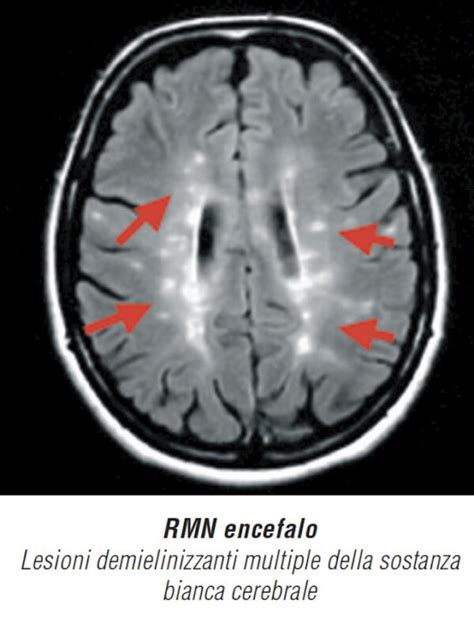

La Sclerosi Multipla è una malattia neurodegenerativa che colpisce il Sistema Nervoso Centrale (SNC), ossia cervello e midollo spinale. La sua caratteristica distintiva è la progressiva degenerazione della mielina, la guaina protettiva che riveste le fibre nervose e che è fondamentale per la corretta trasmissione dei segnali nervosi dal SNC agli organi e ai muscoli. Il nome "sclerosi multipla" deriva dalle cicatrici, o "placche" (sclerosi), che si formano in diverse aree (da qui "multipla") del SNC a seguito del danno alla mielina. Queste lesioni, invisibili all'occhio nudo ma rilevabili tramite tecniche di imaging come la risonanza magnetica (RM), sono come macchie che la malattia lascia sulla guaina isolante, influenzando la conduzione nervosa e, di conseguenza, la funzionalità del corpo.

Una delle sfide nella gestione della sclerosi multipla risiede nell'esistenza di lesioni asintomatiche. Queste aree di demielinizzazione o infiammazione nel SNC non provocano sintomi evidenti e, pertanto, possono passare inosservate sia al paziente che al medico. Tuttavia, la loro presenza è significativa. Studi basati sulla risonanza magnetica hanno rivelato che un numero considerevole di lesioni, spesso anche le più estese, non si accompagna a sintomi neurologici percepibili.

Queste lesioni asintomatiche, sebbene non causino disabilità immediata, rappresentano un indicatore dell'attività della malattia e possono contribuire alla progressione del danno neurologico nel tempo. La loro identificazione tramite RM è fondamentale per monitorare l'evoluzione della SM, valutare l'efficacia delle terapie e identificare precocemente un potenziale peggioramento, anche in assenza di manifestazioni cliniche. L'approccio terapeutico moderno mira a controllare l'attività della malattia, incluse le lesioni asintomatiche, per prevenire o rallentare il danno neurologico a lungo termine.

- Risonanza Magnetica (RM): La RM del cervello e del midollo spinale è lo strumento diagnostico cardine. Permette di visualizzare le lesioni demielinizzanti (placche) e di valutarne la localizzazione e l'estensione. L'uso di mezzo di contrasto (gadolinio) aiuta a distinguere le lesioni attive (infiammate) da quelle più vecchie.